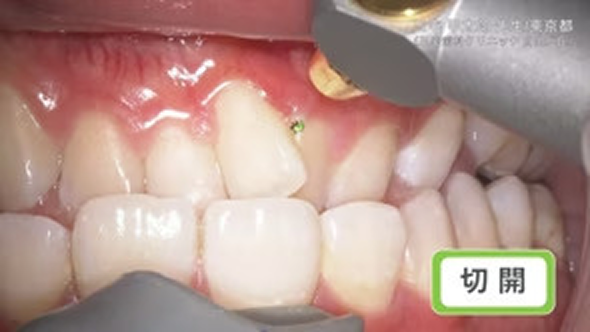

切開

臨床例:炭酸ガスレーザーPRO+/Lite+(最大出力5~7W)を使用した先生の臨床例です。